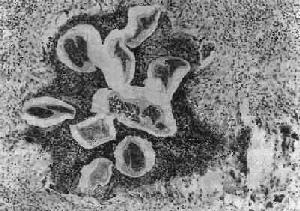

图19-16 丝虫性淋巴管炎 图中可见数个切断的死虫体,周围有嗜酸性脓肿及肉芽肿反应 (2)淋巴结炎:一般由成虫寄居于淋巴结引起,较多见于腹股沟、腘窝及腋窝等处淋巴结。肉眼观,淋巴结显著肿大。镜下,见病变的发展过程与上述淋巴管炎的改变基本相同。死亡虫体钙化后,病变可逐渐纤维化成为瘢痕,影响淋巴液的流通,而导致淋巴淤滞。 (3)淋巴系统阻塞引起的病变:长期反复感染的丝虫性淋巴管炎和淋巴结炎可引起淋巴系统的回流障碍,从而发生一系列改变。 1)淋巴窦及淋巴管扩张:淋巴结内的淋巴窦扩张,形成局部囊状肿块,常见于腹股沟淋巴结,也称腹股沟淋巴结曲张(varicose groin gland),穿刺淋巴液,其中可找到微丝蚴。阻塞远端的淋巴管可见淋巴淤滞而引起曲张,常见于精索、阴囊及大腿内侧,造成组织水肿。淋巴管极度曲张时可使管壁破裂和淋巴液外溢。根据淋巴系统阻塞的部位不同,所溢出的淋巴液性质和病变影响也各异。 当阻塞发生在肠干淋巴管入口的上方或主动脉前淋巴结时,因乳糜液不能回流至乳糜池,则胸导管以下的远端淋巴管皆发生曲张,并形成侧支循环与主动脉侧淋巴结相通。此时如乳糜液经曲张的侧支循环返流至肾盂、输尿管或膀胱的淋巴管而引起破裂时,乳糜液乃溢入尿中,形成乳糜尿。如果乳糜液由此至精索淋巴管流入睾丸鞘膜内,则引起鞘膜乳糜积液;乳糜液也可通过肠系膜淋巴管进入腹腔,则形成乳糜腹水。当阻塞部位发生在肠干淋巴管入口处下方的腰干淋巴管或主动脉侧淋巴结等处时,则对乳糜液回流到胸导管无影响。此时淤滞的淋巴液逆流,则引起相应的淋巴尿、淋巴腹水和鞘膜淋巴积液。 2)象皮肿(elephatiasis):是晚期丝虫病的最突出病变。病变皮肤及皮下组织明显增厚、粗糙、肥大而下垂,皮皱加深,有如大象的皮肤外观,因而得名。有时尚可伴有苔藓样变、棘刺及疣状突起等变化。镜下,表皮角化过度和棘细胞肥厚,真皮及皮下有致密纤维组织极度增生,弹力纤维消失,淋巴管和小血管周围有少许淋巴细胞、浆细胞及嗜酸性粒细胞浸润。真皮淋巴管内皮细胞增生,甚至使管腔完全闭塞,皮下淋巴管壁可有明显肌层肥厚。发病部位最多见于下肢、阴囊、女阴等处,其次为手臂及乳房。以下肢的象皮肿最多见,约占90%,常为双侧性,由踝部和足背部开始,逐渐扩展到小腿甚至大腿,下肢可比正常增粗2~3倍(图19-17)。阴囊象皮肿大小不等,小者如拳头大,大者可大如篮球或更大,甚至可下垂到膝部以下。